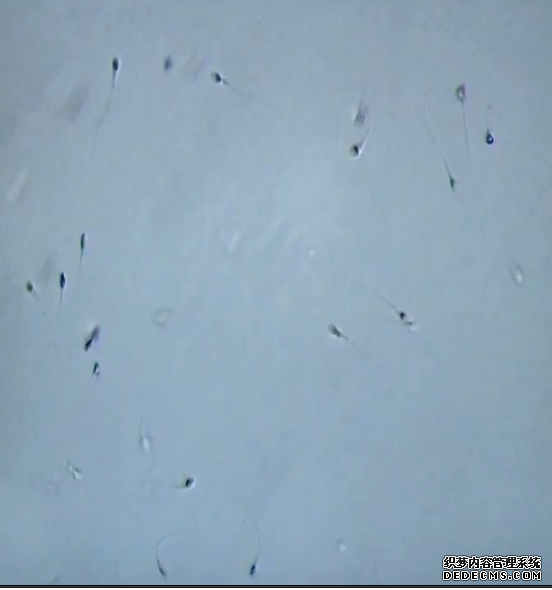

采用精子慢流形态学筛选筛选胞浆内单精子注射技术(SpermSlow? - Approaching physiological ICSI)镜下的单精注射实拍

对于弱精症、少精症患者而言,IMSI技术的出现可以极大地提高受精率,保证胚胎的发育。